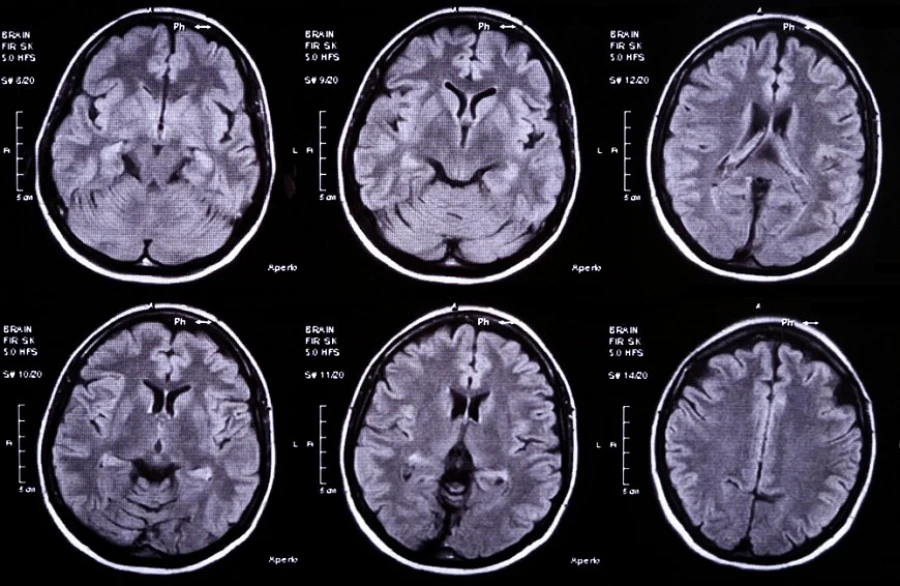

«Ко мне обратилась мать маленького пациента за помощью. Врачи провели две операции по удалению абсцесса головного мозга, но на фоне некомпетентности возникли серьезные осложнения, такие как менингит, который не был выявлен своевременно. В результате МРТ у ребенка обнаружили абсцесс с обеих сторон, однако удалили его только с одной», — написала Кибраева.

По ее словам, повторное хирургическое вмешательство в 10 месяцев не решило проблему, так как абсцесс остался не полностью удаленным.